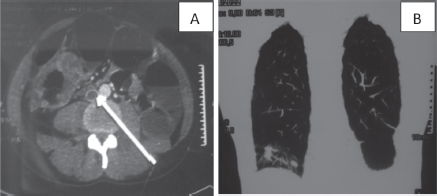

Figure 1. CT scan of a 37-year-old man: (a): Cross-section of inferior vena cava thrombosis (white arrow) and a circumferential mass of the right colon. (b): Frontal section of lung metastases.